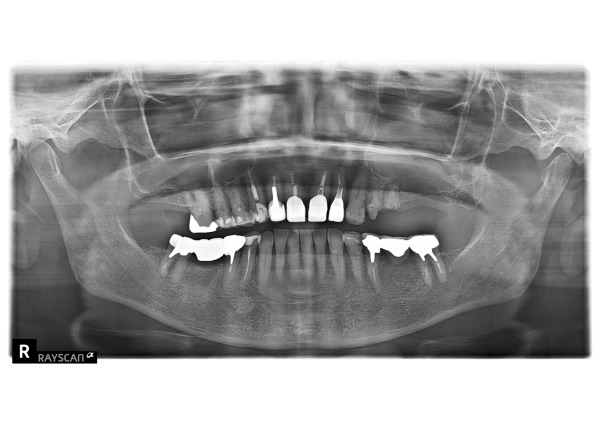

まずエックス線検査をおこなったところ、左上5番が割れていたため、保存ができない状態であることがわかりました。また、左上4番は残すことができても、差し歯にするほど歯の高さは残っていませんでした。

患者様とご相談のうえ、左上4番を入れ歯の支えとして利用し、新しい入れ歯を金属床で製作することになりました。